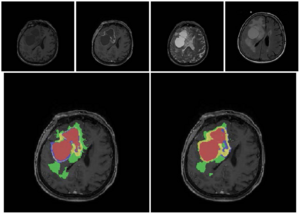

Texture Descriptors to distinguish Radiation Necrosis from Recurrent Brain Tumors on multi-parametric MRI

Publication: Proc SPIE. 2014;9035:90352B. PMID: 24910722 | PDF Authors: Pallavi T, Prateek P, Lisa R, Leo W, Chaitra B, Andrew S, Mark C, Anant M. Institution: Department of Biomedical Engineering, Case Western Reserve University, Cleveland, OH, USA. Background/Purpose: Differentiating radiation necrosis (a radiation induced treatment effect) from recurrent brain tumors (rBT) is currently one of the most clinically challenging problems in care and management of brain tumor (BT) patients. Both radiation necrosis (RN), and rBT exhibit similar morphological appearance on standard MRI making non-invasive diagnosis extremely challenging for clinicians, with surgical intervention being the only course for obtaining definitive "ground truth". Recent studies have reported that the underlying biological pathways defining RN and rBT are fundamentally different. This strongly suggests that there might be phenotypic differences and hence cues on multi-parametric MRI, that can distinguish between the two pathologies. One challenge is that these differences, if they exist, might be too subtle to distinguish by the human observer. In this work, we explore the utility of computer extracted texture descriptors on multi-parametric MRI (MP-MRI) to provide alternate representations of MRI that may be capable of accentuating subtle micro-architectural differences between RN and rBT for primary and metastatic (MET) BT patients. We further explore the utility of texture descriptors in identifying the MRI protocol (from amongst T1-w, T2-w and FLAIR) that best distinguishes RN and rBT across two independent cohorts of primary and MET patients. A set of 119 texture descriptors (co-occurrence matrix homogeneity, neighboring gray-level dependence matrix, multi-scale Gaussian derivatives, Law features, and histogram of gradient orientations (HoG)) for modeling different macro and micro-scale morphologic changes within the treated lesion area for each MRI protocol were extracted. Principal component analysis based variable importance projection (PCA-VIP), a feature selection method previously developed in our group, was employed to identify the importance of every texture descriptor in distinguishing RN and rBT on MP-MRI. PCA-VIP employs regression analysis to provide an importance score to each feature based on their ability to distinguish the two classes (RN/rBT). The top performing features identified via PCA-VIP were employed within a random-forest classifier to differentiate RN from rBT across two cohorts of 20 primary and 22 MET patients. Our results revealed that, (a) HoG features at different orientations were the most important image features for both cohorts, suggesting inherent orientation differences between RN, and rBT, (b) inverse difference moment (capturing local intensity homogeneity), and Laws features (capturing local edges and gradients) were identified as important for both cohorts, and (c) Gd-C T1-w MRI was identified, across the two cohorts, as the best MRI protocol in distinguishing RN/rBT. Funding:

Representative T1-w MR images for rBT (a) and RN (f). Figures 3 (b), (c) and (g), (h) outlined in green, represent top performing features (HoG (red, magenta arrows show top 2 prominent directions), and Laplacian inverse moment (red shows more heterogeneity)) for rBT, RN respectively. Figures 3 (d), (e) and (i), (j), outlined in orange, represent the worst performing features (S5L5 and L5E5 (laplacian) Laws features) for rBT and RN respectively for primary BT patients. |